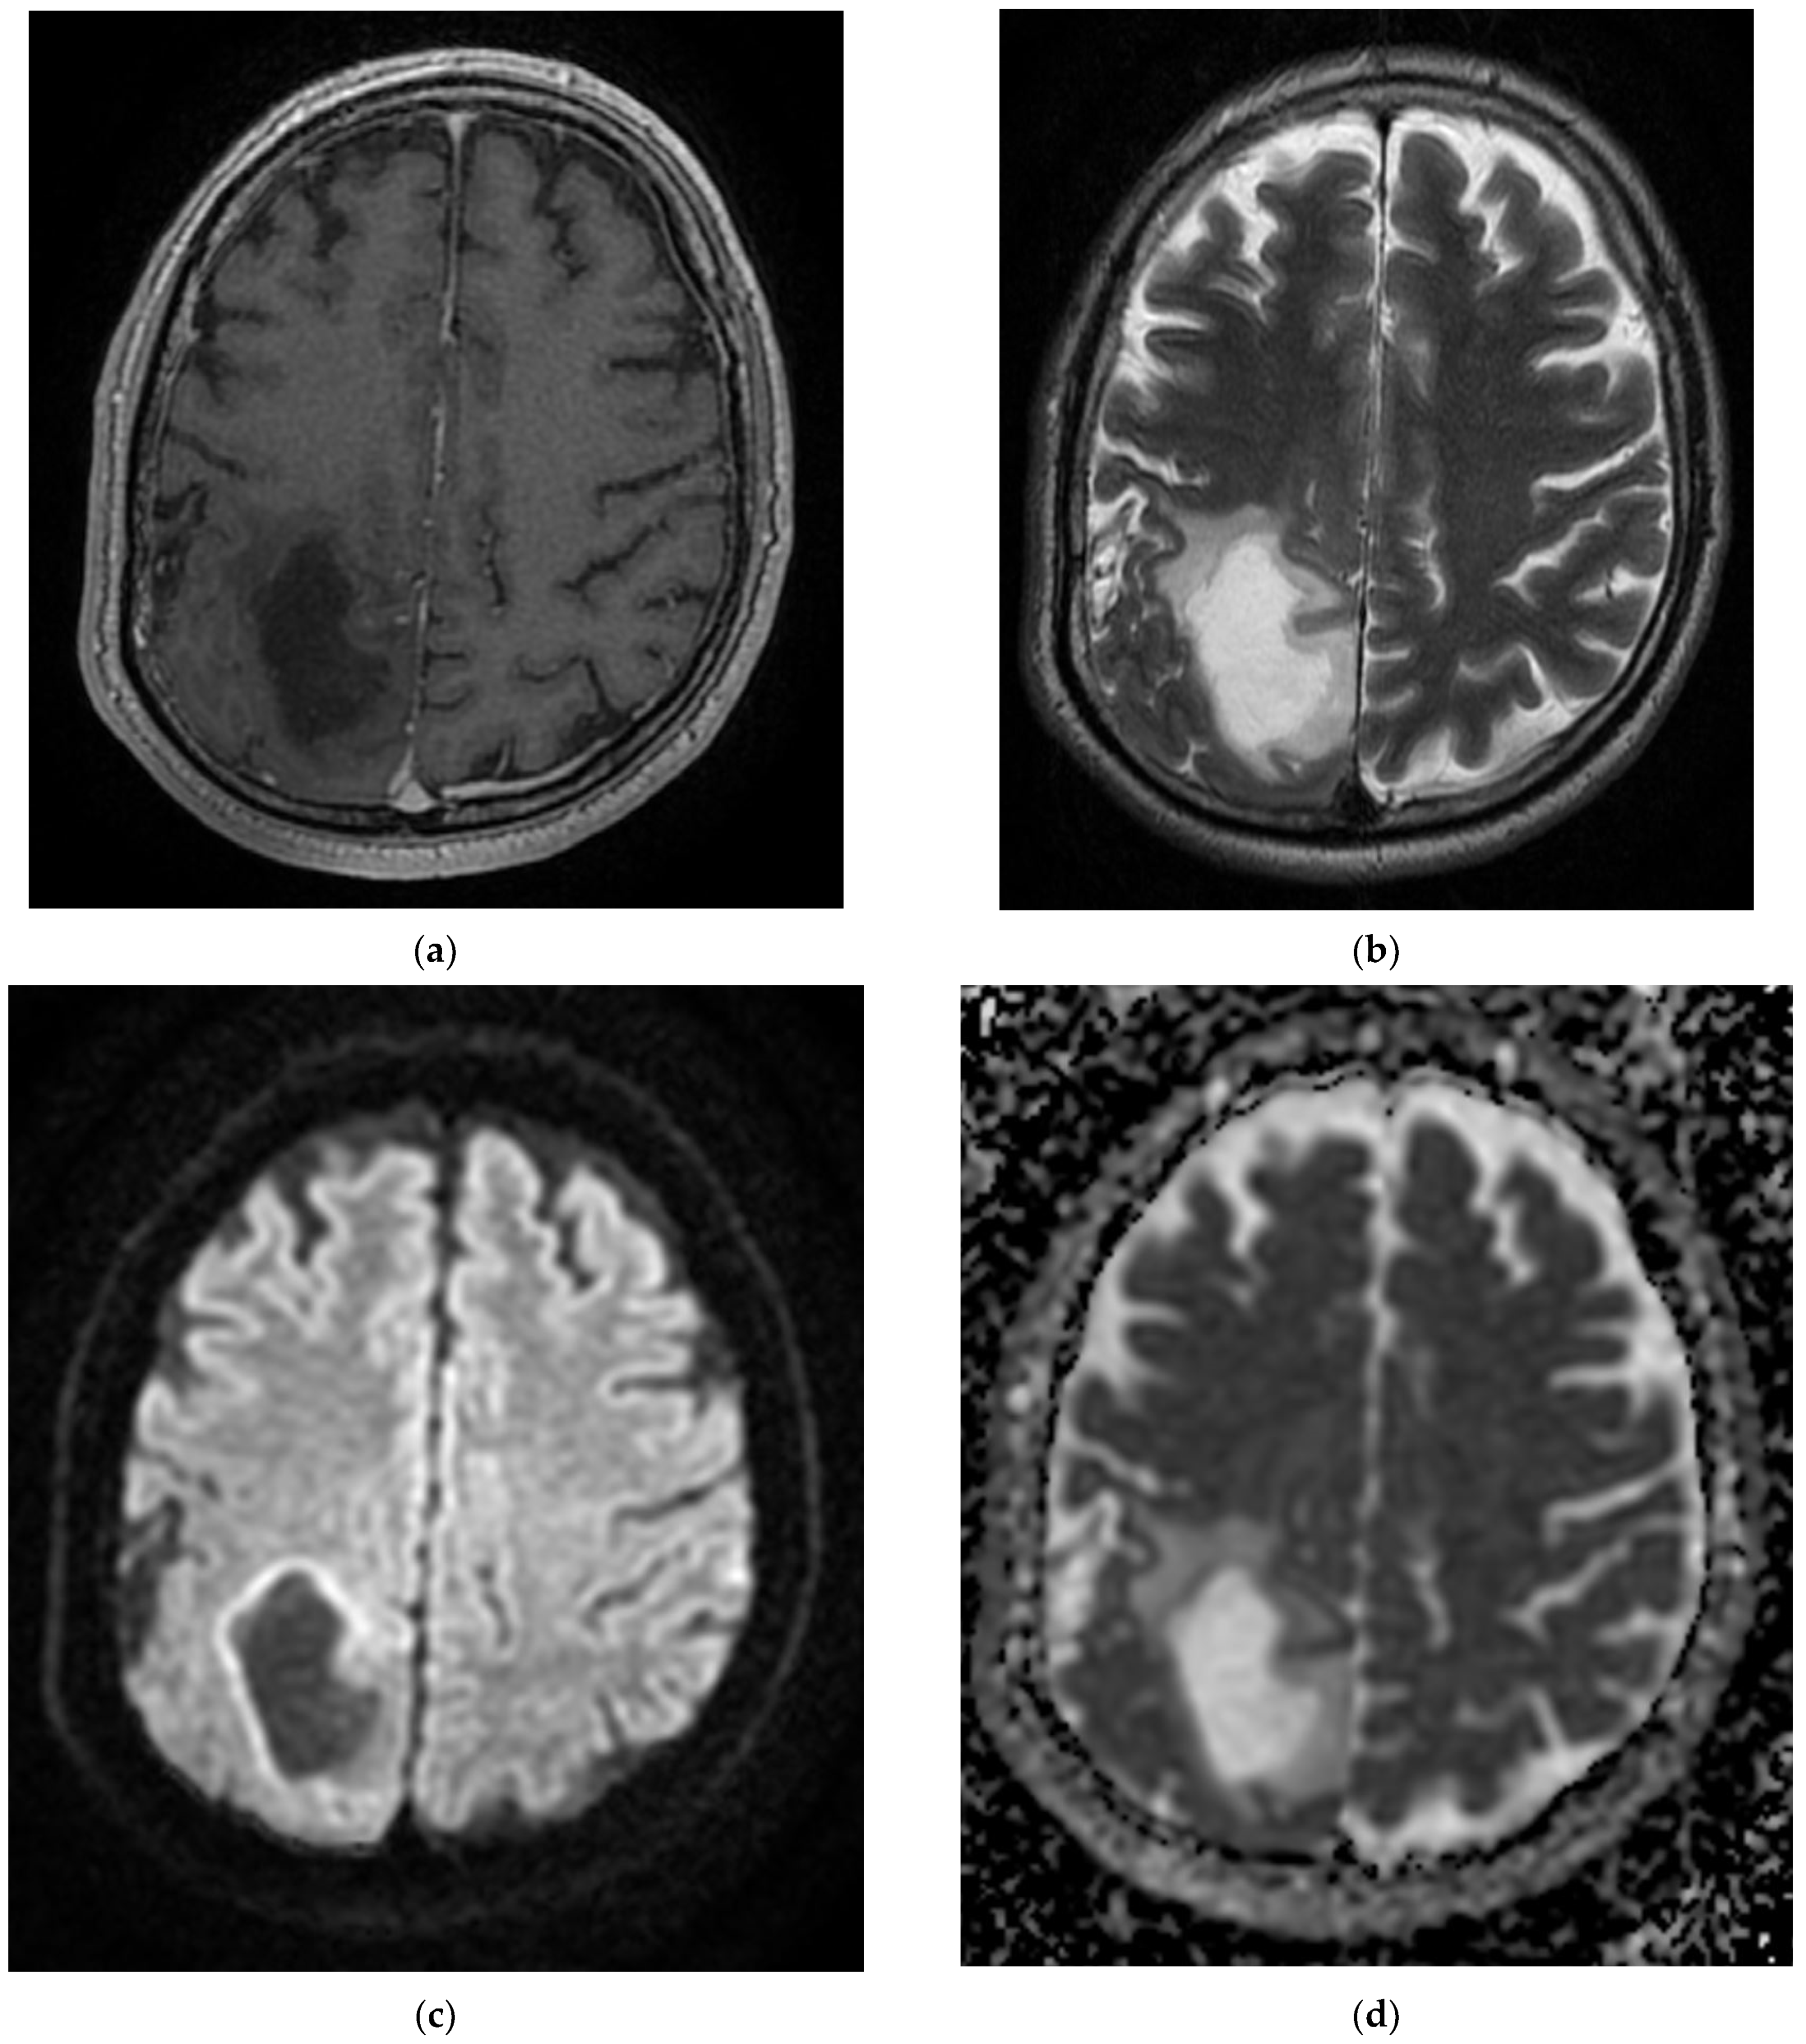

On admission, the patient had a brain CT scan, which showed acute ischemic stroke in the left MCA with an ASPECTS score of 9 points. On day 2 of hospitalization, the patient underwent a brain MRI, which showed acute ischemic stroke in the superficial and deep left Sylvian territories, in the superficial border territories of the middle cerebral artery/posterior cerebral artery, and in the middle cerebral artery/left anterior cerebral artery, with a small area of hemorrhagic transformation in the lenticular nucleus (Figure 2). On day 7 of hospitalization, the patient developed a cough with mucopurulent sputum, became trachea–bronchial loaded, and was tested by RT-PCR for SARS-CoV-2, with the result being positive. The patient was transferred to a hospital for supporting COVID-19.

Figure 2. MRI images of the Case 2 patient shows extended foreshores, irregularly delimited, T2-FLAIR hyperintense (a,b), with restriction of marked diffusion (c,d), confirmed by a hypointense signal on the map of apparent diffusion (d), situated in the cortical–subcortical frontal–parietal–occipital and left insular part, with capsular and lenticular extension. Centimetric intralesional focal signal point SWAN sequence was associated in the left lenticular nucleus (e). These characteristics are suggestive of acute ischemic stroke on the left superficial and profound Sylvian territory, and on the superficial territories of the border between the median cerebral artery/posterior cerebral artery and medium cerebral artery/left anterior cerebral artery (ad), with a small area of hemorrhagic transformation in the lenticular nucleus (e).